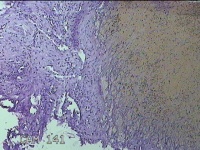

左卵巢囊肿

性别

女

年龄

47岁

临床诊断

左附件囊肿

一般病史

不规则阴道流血20余天。

标本名称

大体所见

灰白暗红色囊壁样组织4.3x1.3x0.3cm一块,表面光滑,因已切开,囊内容物已流失,囊壁厚0.1cm。

良性病变。